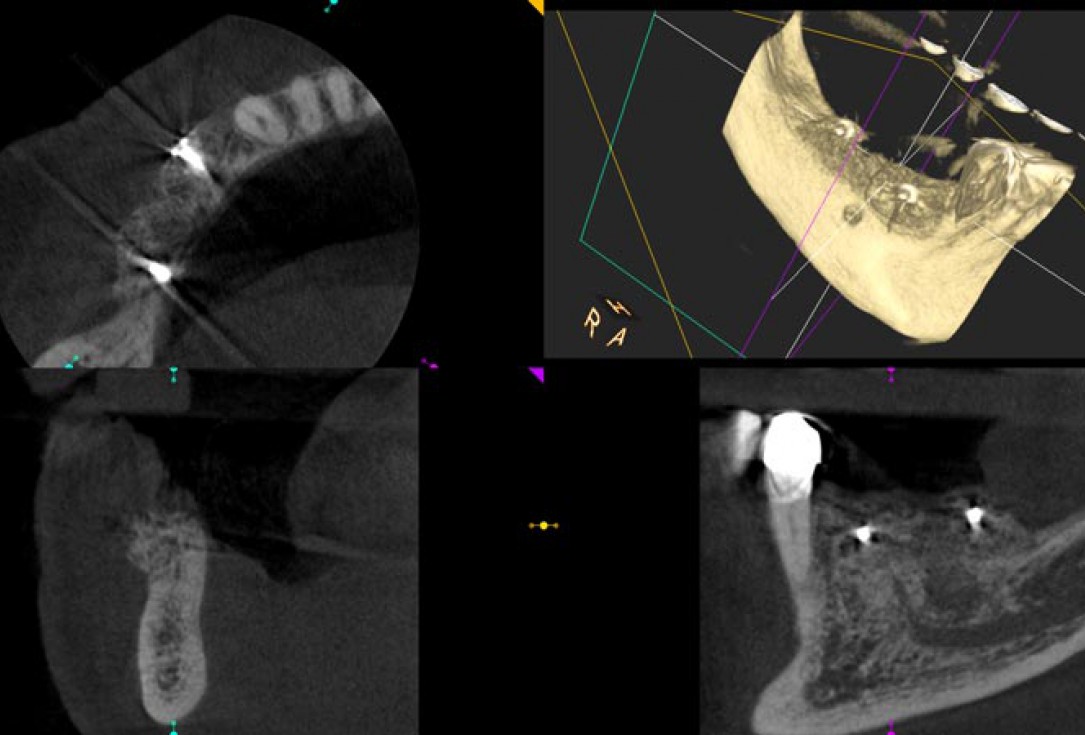

11/14 - CBCT scan post implantation

Block augmentation with maxgraft® in the mandible - PD Dr. Dr. F. Kloss